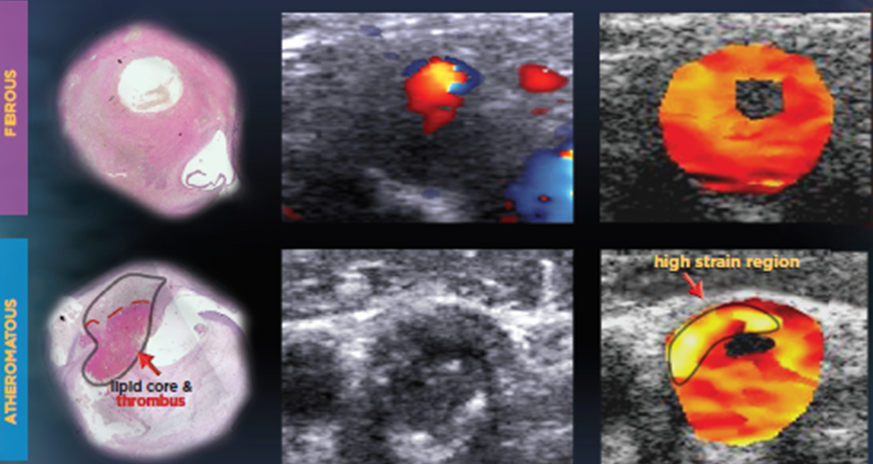

Figure: Histology (right), conventional b-mode incl Doppler (middle), and elastogram (right) of a fibrous carotid plaque (upper row) and atheromatous plaque (lower row),

revealing high strain values in the lipid core and low strain values in fibrous plaque components.